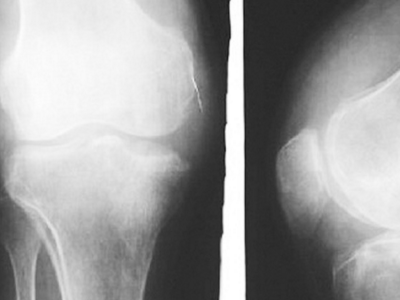

核心提示:滑膜炎是一种多发性疾病,其发病部位主要在膝关节。因为膝关节是人体滑膜最多,关节面最大和结构最复杂的关节,而且也是遭受损伤和感染的机会较多的部位,无论对患者和对社会的危害都较大,因此得了滑膜炎就要及时进行治疗。

滑膜炎是滑膜炎症刺激所致。膝盖有大多数关节滑膜、膝关节滑膜炎很容易被见到。滑液细胞的分泌物可以润滑和营养关节,所产生的热量是因为膝关节运动的滑液和血液循环。当关节是受内部和外部因素,滑膜反应,导致拥塞或水肿,渗出的液体,表现为关节肿胀、疼痛、功能障碍。也可以说是关节积液,即滑膜炎症。